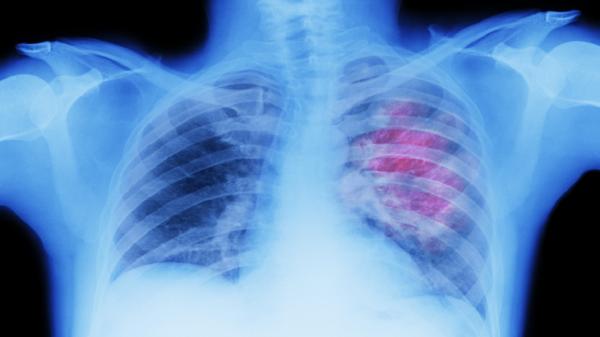

وكان العلماء في معهد فرانسيس كريك يدرسون سرطان الرئة، السبب الرئيسي للوفيات المرتبطة بالسرطان على مستوى العالم، لفهم سبب استجابة بعض المرضى بشكل أفضل من غيرهم للعلاج المناعي.

ومن خلال الدراسة المنشورة في مجلة Nature، وجدوا أن بقايا الخلايا القديمة يمكن تنشيطها بواسطة الخلايا السرطانية. واكتشفوا أن هذا يمكن أن يساعد عن غير قصد جهاز المناعة على استهداف الورم ومهاجمته.

وأفاد العلماء أن هذه النتائج "الرائعة" يمكن استخدامها لمساعدة المزيد من الناس على النجاة من سرطان الرئة من خلال تعزيز علاج السرطان أو حتى الوقاية منه.